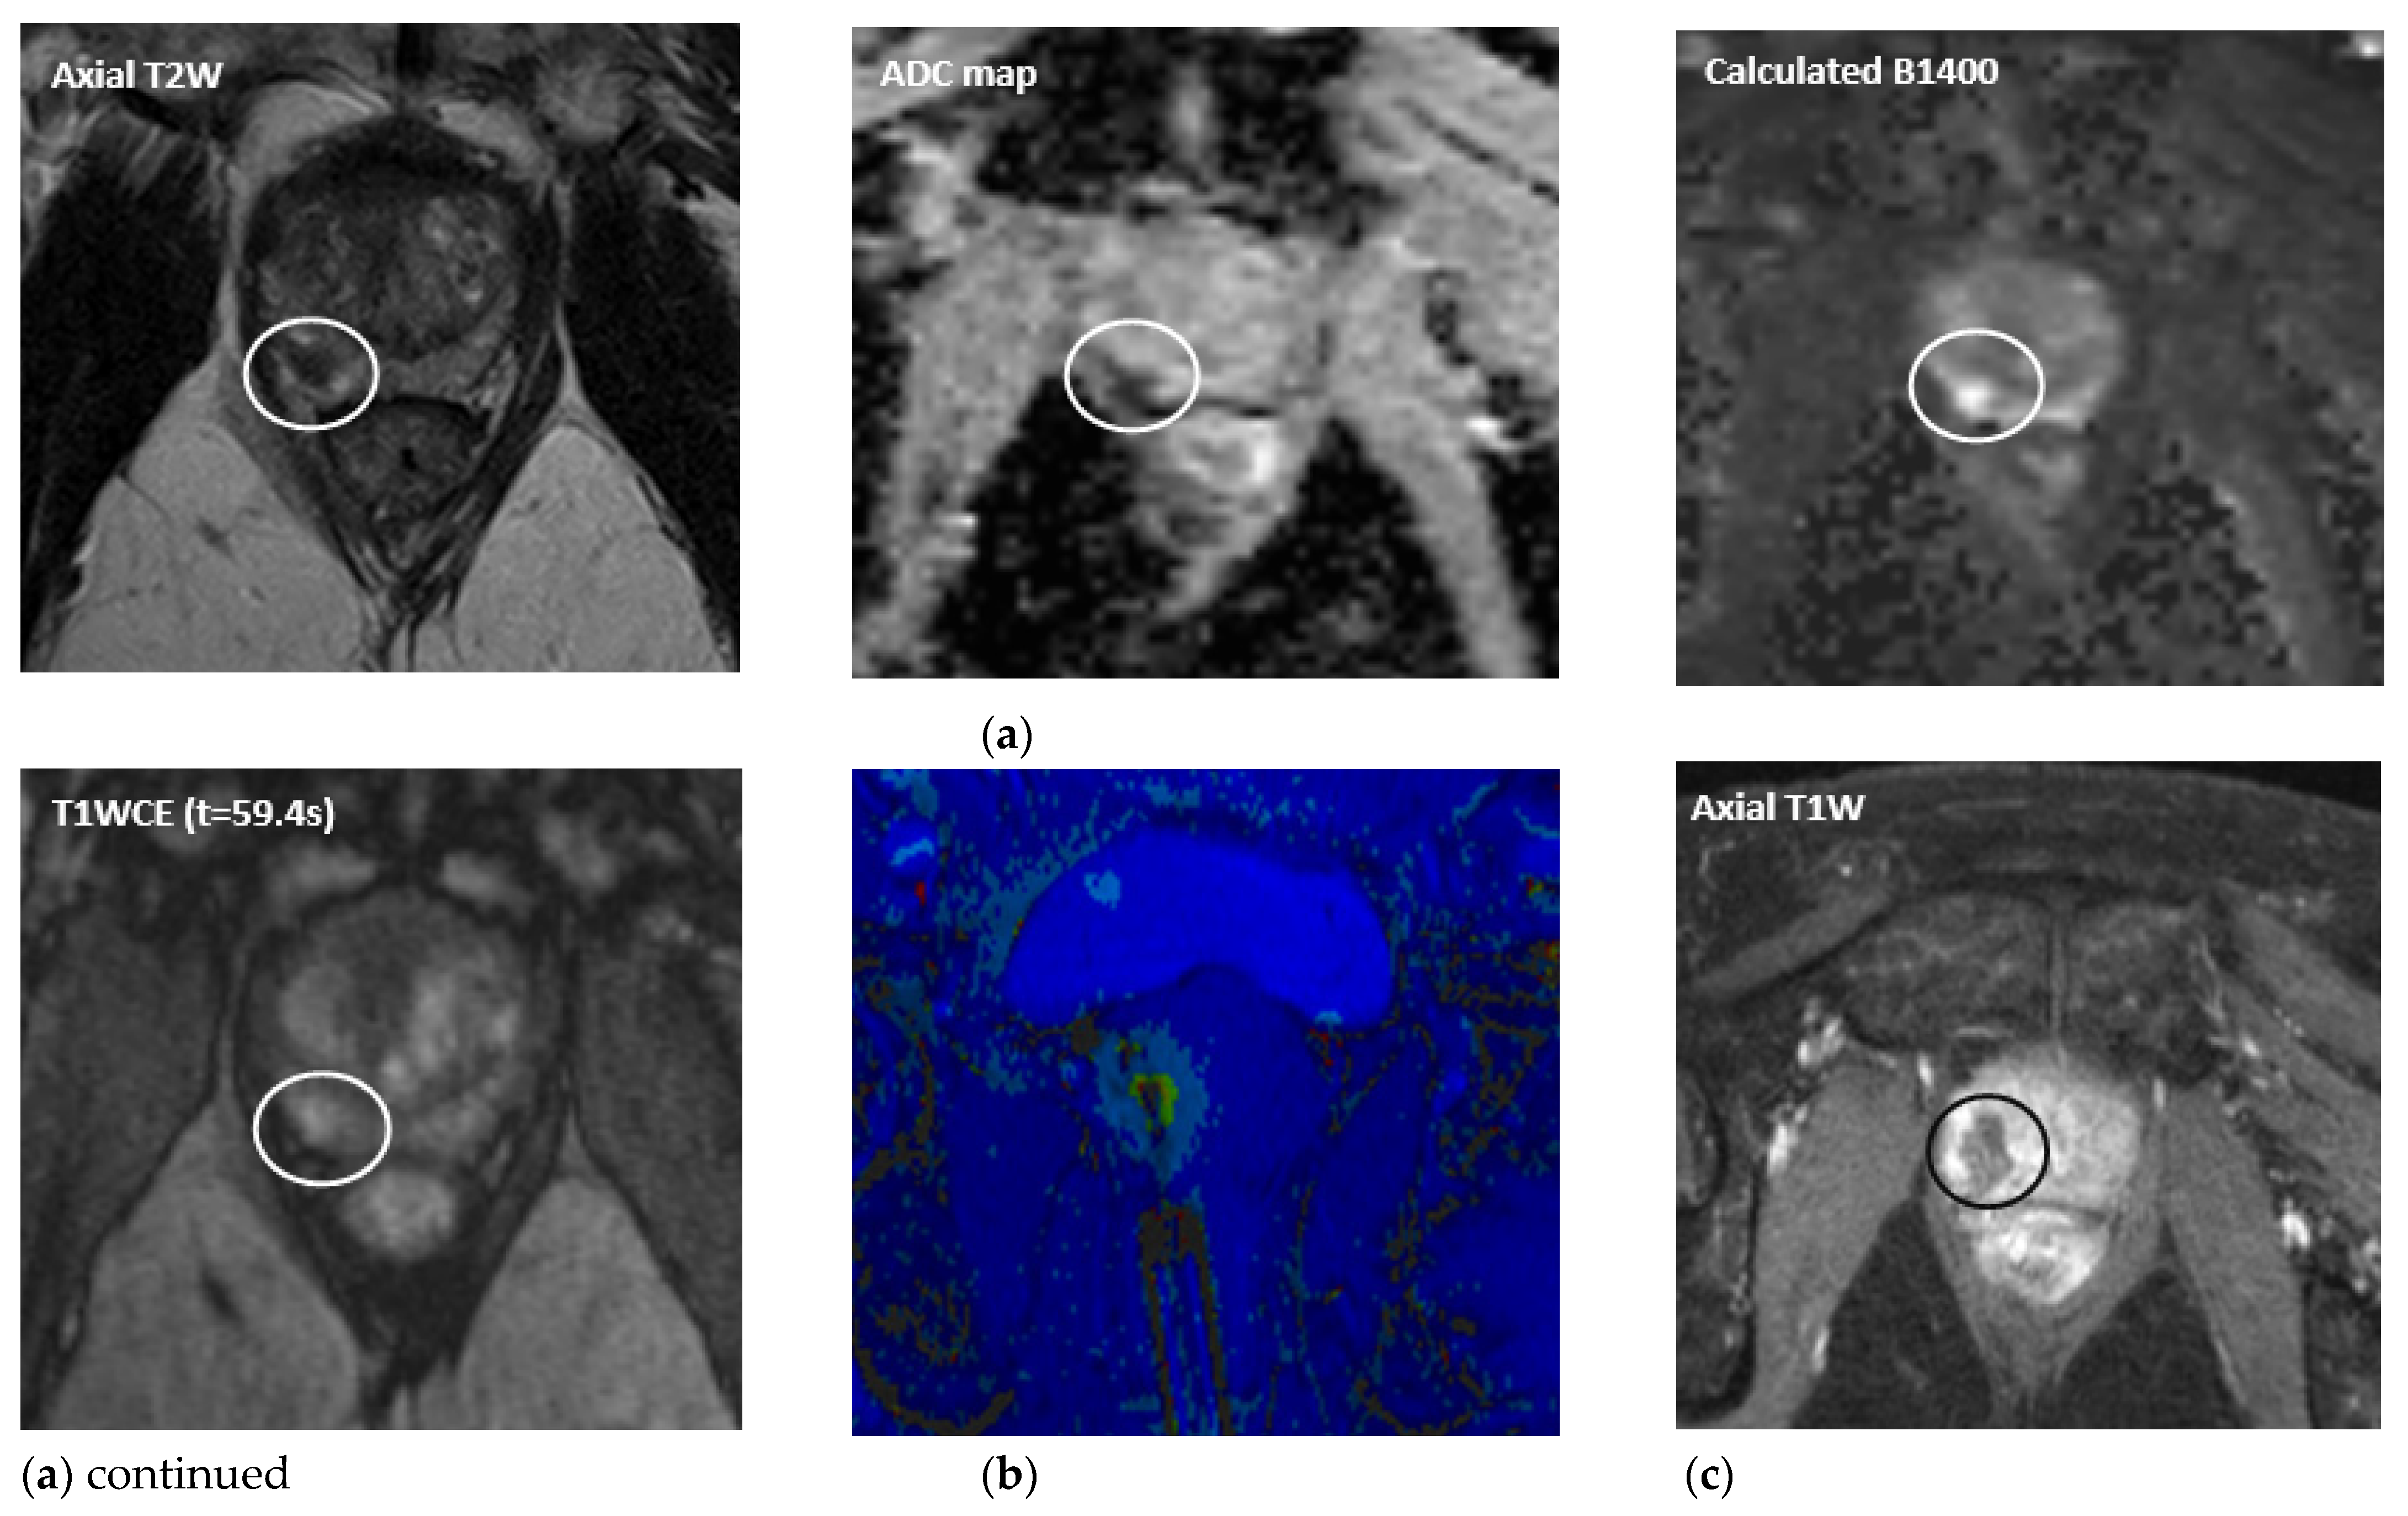

- Oto, A.; Sethi, I.; Karczmar, G.; McNichols, R.; Ivancevic, M.K.; Stadler, W.M.; Watson, S.; Eggener, S. MR Imaging–guided Focal Laser Ablation for Prostate Cancer: Phase I Trial. Radiology 2013, 267, 932–940. [Google Scholar] [CrossRef]

- Mehralivand, S.; George, A.K.; Hoang, A.N.; Rais-Bahrami, S.; Rastinehad, A.R.; Lebastchi, A.H.; Ahdoot, M.; Siddiqui, M.M.; Bloom, J.; Sidana, A.; et al. MRI-guided focal laser ablation of prostate cancer: A prospective single-arm, single-center trial with 3 years of follow-up. Diagn. Interv. Radiol. 2021, 27, 394–400. [Google Scholar] [CrossRef]

- Eggener, S.E.; Yousuf, A.; Watson, S.; Wang, S.; Oto, A. Phase II Evaluation of Magnetic Resonance Imaging Guided Focal Laser Ablation of Prostate Cancer. J. Urol. 2016, 196, 1670–1675. [Google Scholar] [CrossRef]